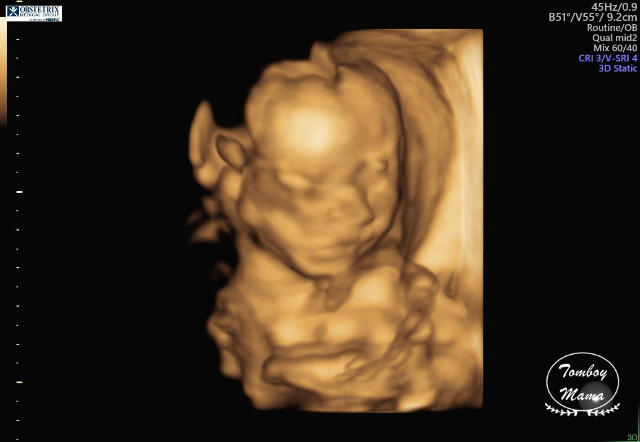

그리고 3D로 만나본 튼튼이. 사진들이 살짝 무섭긴 한데, 나중에 태어난 후의 모습이랑 비교하면 많이 비슷하려나 궁금하다. (찾아보니 입체 초음파 사진으로 생후 모습을 분석해 보여주는 한국 스타트업의 [베이비페이스]라는 프로그램이 있더라고요! 해보고 싶었는데, 25주 이상의 입체 초음파 사진이 필요하다고 해서 전 포기했어요... 저처럼 궁금하신 분들 참고하세요~)